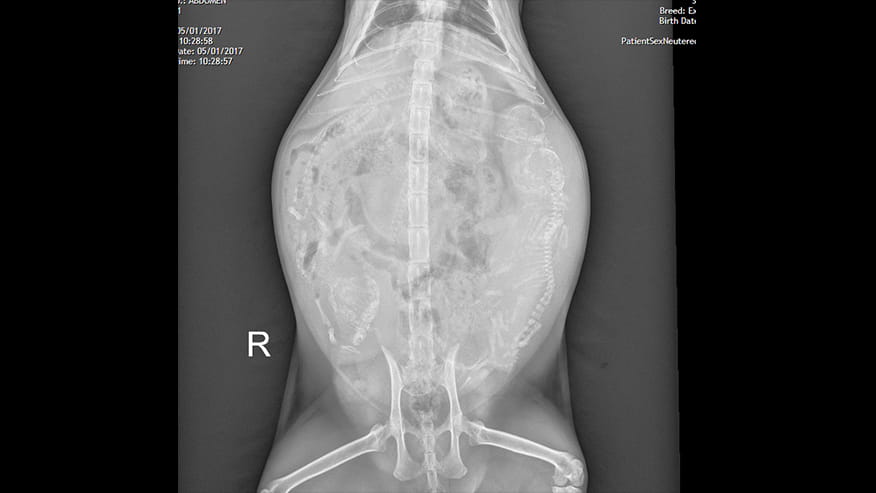

• Digital Radiology at VCA Lovers Lane Animal Hospital

Our hospital is proud to offer state-of-the-art digital radiology services. Digital x-rays are essentially film-less x-rays. Traditional x-rays use photographic film to capture images whereas digital x-rays use a digital image capture device (computer) to record the x-ray image.... Read more